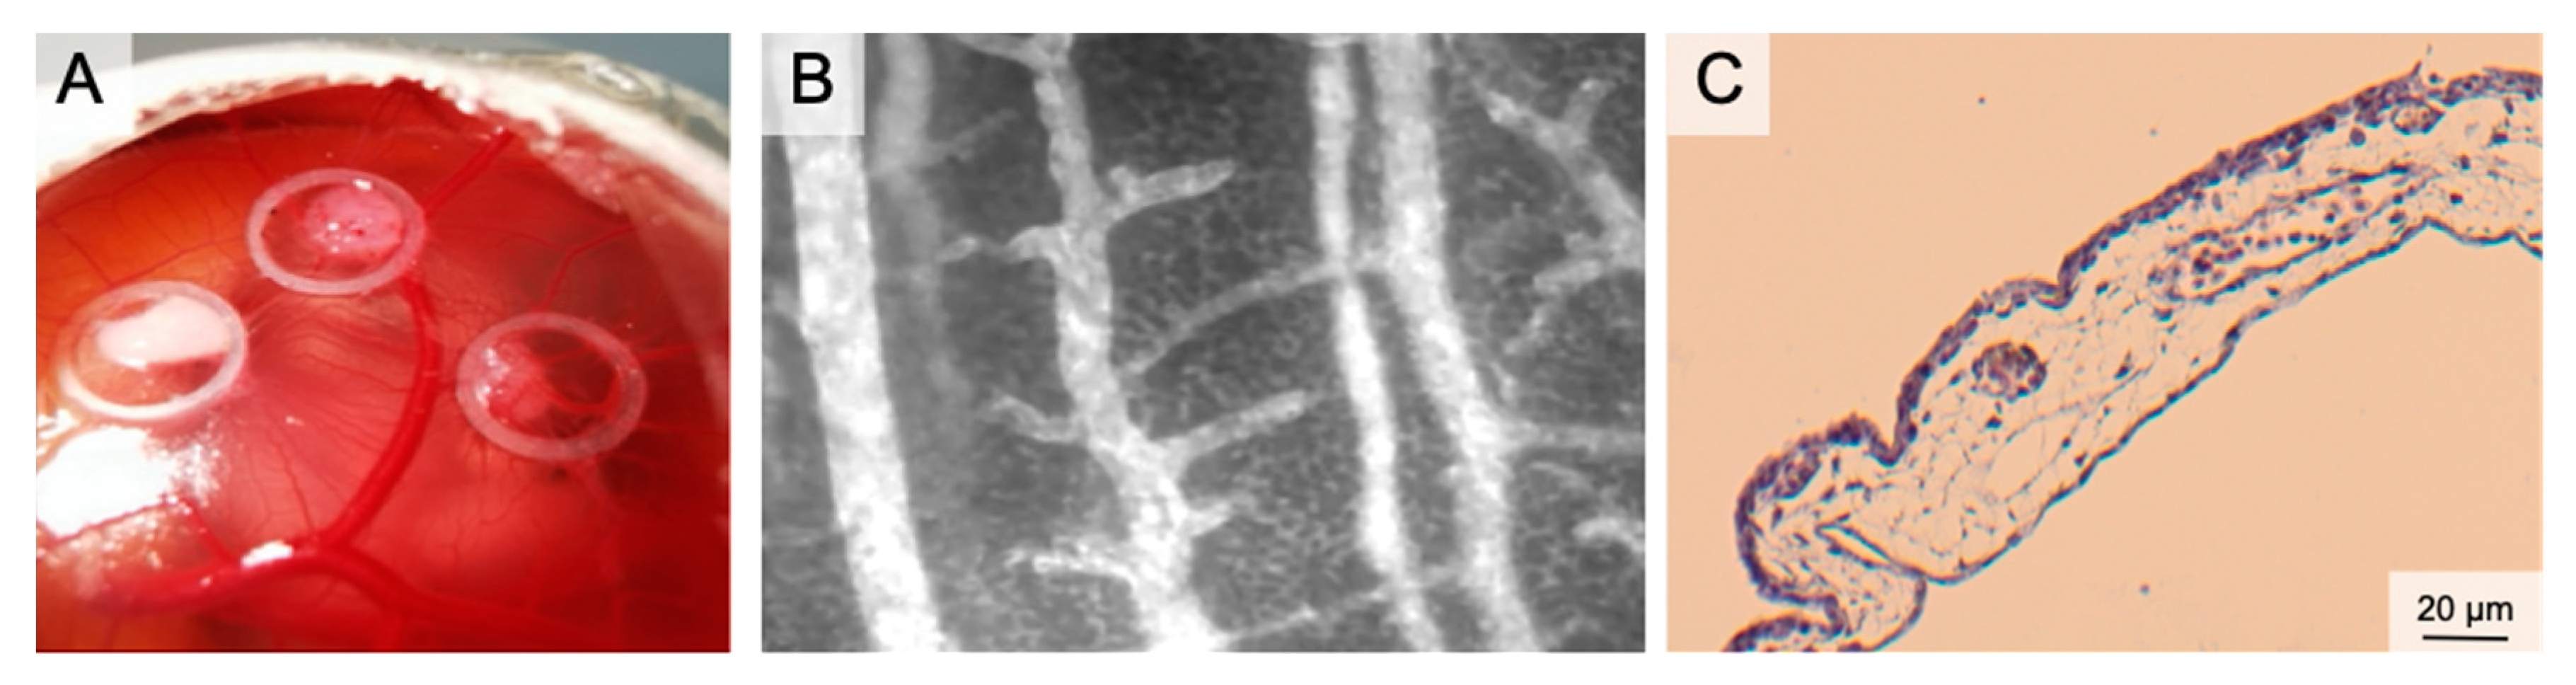

Figure 3.

The Chorion Allantois Membrane Assay. (A) Representative macroscopic image of the CAM vessels after implantation of squamous cell carcinoma cells. The tumors grow within silicone rings. (B) Intravital microscopy following iv FITC-dextran injection. The image depicts venules and arterioles surrounded by the dense capillary network. (C) HE staining of the CAM membrane showing well-vascularized connective tissue between the low epithelial layers.